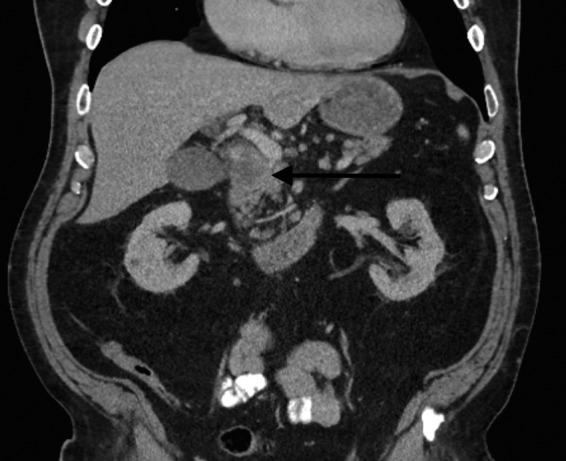

Pancreatic adenosquamous carcinoma (ASC) is an uncommon subtype of pancreatic neoplasm, representing 1-4% of all pancreatic cancers. Given the rarity of this tumor, there is no well-established standard of care regarding treatment. We present the case of a BRCA2-deficient patient who responded tremendously well to a combination of gemcitabine and cisplatin therapy. A 66-year-old Caucasian man presented with a 2-week duration of progressively worsening clay-colored stools, tea-colored urine, and jaundice. Computed tomography scan of the abdomen revealed a 4-cm mass at the head of the pancreas. Preoperative carbohydrate antigen (CA) 19-9 was 255 U/mL (normal <37 U/mL). The patient underwent an uncomplicated pylorus-preserving pancreaticoduodenectomy with pathology revealing 11/12 positive lymph nodes, positive resection margins, perineural invasion, lymphovascular invasion, and positive disease in two distant perihepatic lymph nodes. The patient received one cycle of combination of gemcitabine and abraxane, was subsequently found to be BRCA2 deficient, and completed five cycles of gemcitabine and cisplatin thereafter. CA 19-9 before chemotherapy was 203 U/mL. Postchemotherapy CA 19-9 was 13 U/mL. As of today, the patient continues to do well 22 months postresection without radiographical or gross evidence of disease. Gemcitabine in combination with a platinum agent shows promise in the treatment of pancreatic ASC, particularly in setting of BRCA2 deficiency.

胰腺腺鳞癌(ASC)是一种罕见的胰腺肿瘤亚型,占所有胰腺癌的1%-4%。鉴于这种肿瘤的罕见性,目前尚无成熟的治疗标准。我们报告一例BRCA2基因缺陷患者,其对吉西他滨和顺铂联合治疗反应良好。一名66岁的白人男性,出现持续2周的进行性加重的陶土样便、茶色尿和黄疸。腹部计算机断层扫描显示胰腺头部有一个4厘米的肿块。术前糖类抗原(CA)19-9为255 U/mL(正常<37 U/mL)。患者接受了保留幽门的胰十二指肠切除术,手术顺利,病理显示12个淋巴结中有11个阳性,切缘阳性,存在神经周围侵犯、淋巴管侵犯,且两个远处肝周淋巴结有疾病阳性。患者接受了一个周期的吉西他滨和白蛋白结合型紫杉醇联合治疗,随后发现BRCA2基因缺陷,此后完成了五个周期的吉西他滨和顺铂治疗。化疗前CA 19-9为203 U/mL。化疗后CA 19-9为13 U/mL。截至目前,患者在切除术后22个月情况良好,无影像学或肉眼可见的疾病证据。吉西他滨与铂类药物联合在胰腺ASC的治疗中显示出前景,尤其是在BRCA2基因缺陷的情况下。